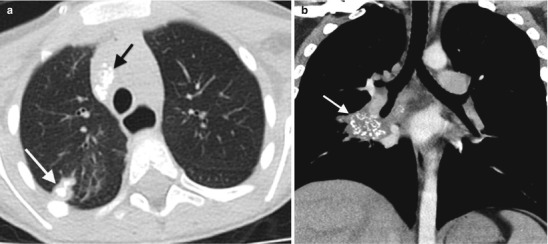

Lymphadenopathy (present in 92 %) with or without a visible Ghon focus is the radiographic hallmark of TB infection and usually involves the hilar and paratracheal regions. The Ghon focus may be too small to be radiographically visible but can also undergo caseation and calcify (Fig. 13.17). Disease progression may occur at the site of Ghon focus, within the regional lymph nodes, or following disease spread (Fig. 13.18). Parenchymal involvement in primary pulmonary TB most commonly appears as homogeneous consolidation, although it can appear patchy, linear, nodular, and mass-like. Caseation necrosis, liquefaction, or calcifications can be seen within the consolidation and can progress into extensive lung damage (Marais et al. 2004) (Fig. 13.19). Enlarged and edematous hilar, paratracheal, and subcarinal lymph nodes may cause compression of the adjacent bronchus and can lead to hyperinflation or atelectasis of the affected lung segment. Contrast-enhanced CT shows a characteristic appearance consisting of central areas of low attenuation with peripheral rim enhancement and obliteration of perinodal fat (Kim et al. 1997) (Fig. 13.20).

Fig. 13.19.

Progression of Ghon focus. CT scan images from two different patients showing advanced progression of lung parenchymal disease from dense consolidation with ischemic changes (a) and cavitary necrosis with cyst formation (b)

Fig. 13.20.

Progression of lymph node disease. Image (a) demonstrates an enlarged right paratracheal lymph node effacing the trachea, with central hypoattenuation and peripheral contrast enhancement. Image (b) shows extensive subcarinal lymph nodes effacing the bronchi, especially the right mainstem bronchus (white arrow)